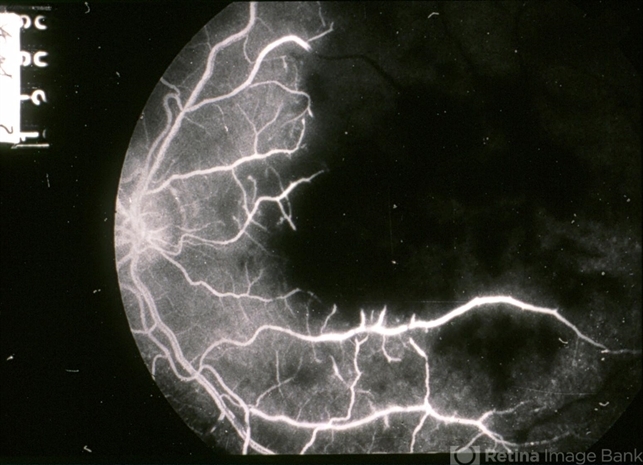

- Amikacin retinal toxicity, capillary closure

- Extensive capillary closure after intravitreal amikacin injection.